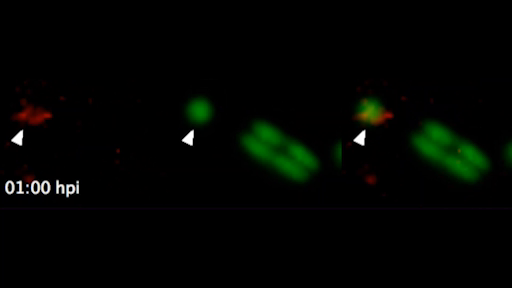

Listen to the following audio clip from the BBC’s Inside Science programme. Liz Sockett from the University of Nottingham talks about research using Bdellovibrio bacteriovorus to treat Shigella infections in zebrafish. You may also like to watch Video 2 which shows a Bdellovibrio bacteriovorus bacterium (labelled in red) preying on a Shigella bacterium (labelled in green) inside a zebrafish larva.